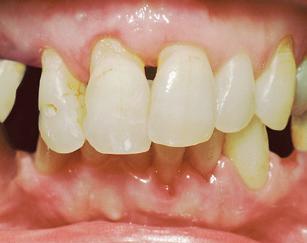

The perio-ortho systemic link has been clearly connected through the years.

As

healthcare providers, we should focus on both disease prevention and treatment modalities when dealing with periodontal disease.

It is now clear that orthodontic health is vital for periodontal and systemic health. Therefore, orthodontic treatment should be one of the treatment options considered in prevention plans, as well as restorative plans in dentistry. Evidence based dentistry has shown that more than just three millimeters of crowding can be a host factor for periodontal disease. Therefore, preventative treatment to avoid periodontal issues should consist of placing the teeth in proper alignment, including reduction or elimination of crowding. Research has also shown that there is significantly greater plaque accumulation in crowded areas. Interestingly, research also indicates that the bacteria present in crowded areas consistently represents more species of periodontopathogens than bacteria from non-crowded regions. The pathogens are more virulent in the areas that are more crowded because they become anaerobic, meaning they grow in the absence of oxygen. As plaque accumulation increases subgingivally, or beneath the gums, the amount of periodontopathogens increases. 2

If we can reduce crowding, then we can reduce aggressive periodontal pathogenic bacteria, which can subsequently decrease the risk of periodontal disease as well as the inflammatory disease processes in the rest of the body. Our currently preferred options for reducing crowding include traditional braces and clear aligner therapy, such as Invisalign®